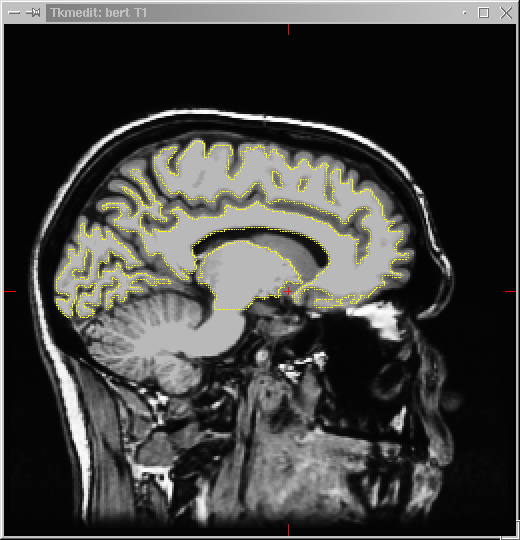

The first step of Process Volume is Normalize Intensities. This step takes approximately 20 minutes per hemisphere processor time. The output of the Normalize Intensities step is the T1 volume (intensity normalized volume). The T1 volume can be viewed in Tkmedit as for the orig volume (click on the ‘T1’ radio button and then the Volume button) when the Process Volume procedure is complete. A dialog box will inform you the sequence is finished:

The T1 volume is now ready to view:

2) In TkMedit, you’ll load the T1 volume as the second volume:

TkMedit reads a maximum of two volumes at a time. The images in the first buffer can be edited and saved, whereas images loaded into the second buffer are view-only and cannot be edited. The second buffer is useful for comparative analyses, (e.g. when the first buffer has segmented white matter (wm volume) and the second buffer has the original T1 images). It is recommended that you load in the T1 volume as your second volume (auxiliary to the wm volume) to refer to when you make your edits.